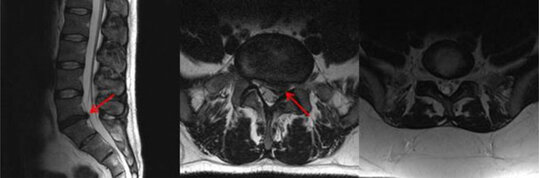

Bandscheibenvorfälle

Bei einem Bandscheibenvorfall kommt es zu einem Austritt von Bandscheibenanteilen in den Wirbelkanal und kann an der Hals-, Brust- und Lendenwirbelsäule entstehen. Dieser ausgetretene Bandscheibenanteil kann starke Schmerzen verursachen und auch z. B. zu Lähmungen, Gefühlsstörungen oder einer gestörten Blasen- und Darmentleerung führen. Eine operative Therapie kann indiziert sein, wenn durch eine konservative Therapie mit Schmerzmitteln und Physiotherapie langfristig keine Besserung erzielt werden kann oder in Fällen von Lähmungen oder gestörter Blasen- oder Darmentleerung (Inkontinenz). Die Operationsmethode richtet sich nach der Lokalisation und Ausprägung des Bandscheibenvorfalls. Im Bereich der Halswirbelsäule wird die Operation z. B. in den meisten Fällen von vorne und im Bereich der Lendenwirbelsäule meistens von hinten durchgeführt. Sollte zusätzlich eine mechanische Instabilität vorliegen, ist ggf. zusätzlich eine Stabilisierung durch Schrauben, Platten etc. erforderlich (s.u.).